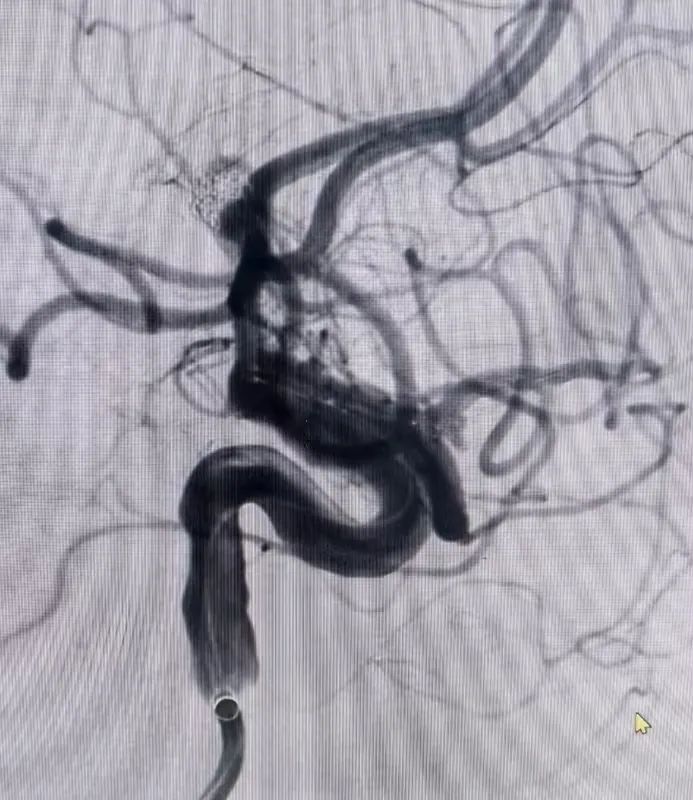

面对大动脉瘤且血管条件差的患者(腹主动脉S型迂曲,右侧颈总动脉II型牛角弓),以及颈内动脉多发动脉瘤的不同患者(C5-C7有5枚动脉瘤),吴全主任团队运用密网支架对症治疗,用一个支架巧妙解决大动脉瘤或多个动脉瘤难题,效果良好,患者短时间内快速恢复。